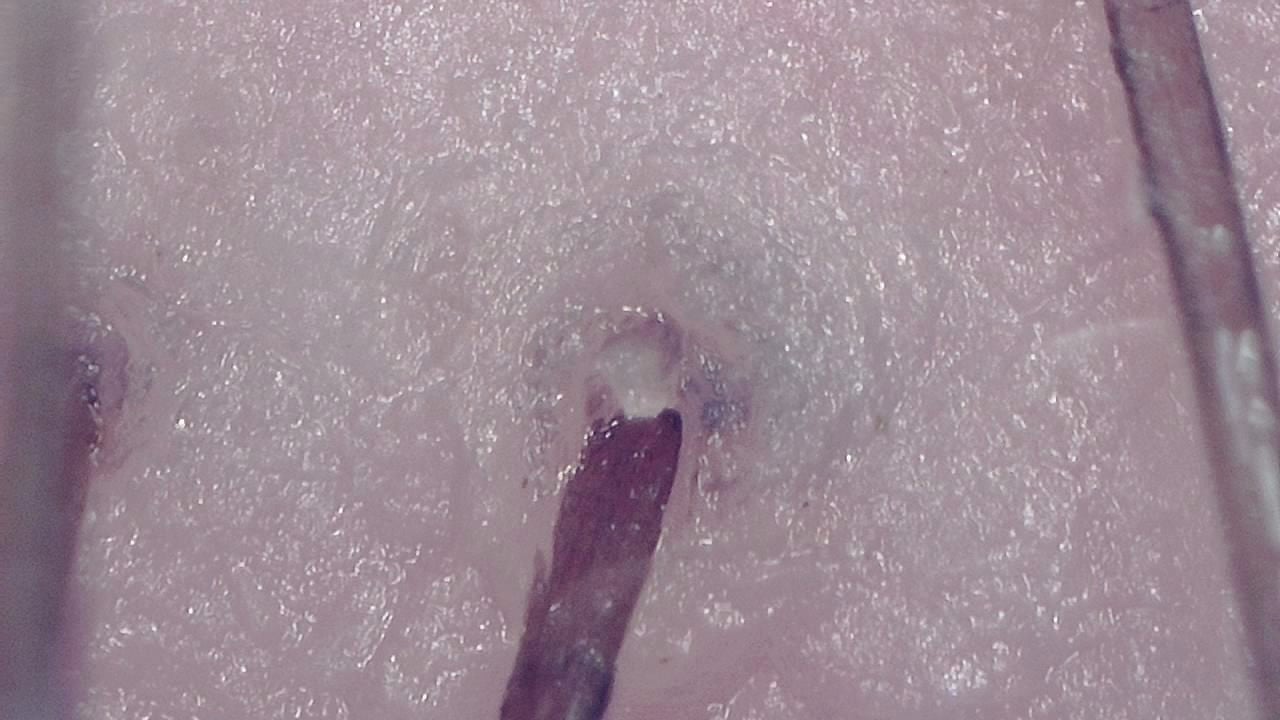

Portable magnified viewing for scalp surface, hair shafts, follicular openings, and visual documentation over time.

Trichoscopy is a non-invasive visual examination technique used by trained professionals to observe the scalp surface and hair shafts. Smart G-Scope provides a portable USB workflow for magnified viewing and image capture.

The device can support documentation of hair shaft appearance, scalp surface features, follicular openings, and visible changes over time. It is most useful when images are captured under consistent lighting and positioning.

What you can observe

- Hair shafts and visible shaft diameter variation.

- Scalp surface texture and visible follicular openings.

- Visible scaling, residues, or surface changes that need professional interpretation.

- Magnified viewing of hair shafts, scalp surface, and visible follicular openings.